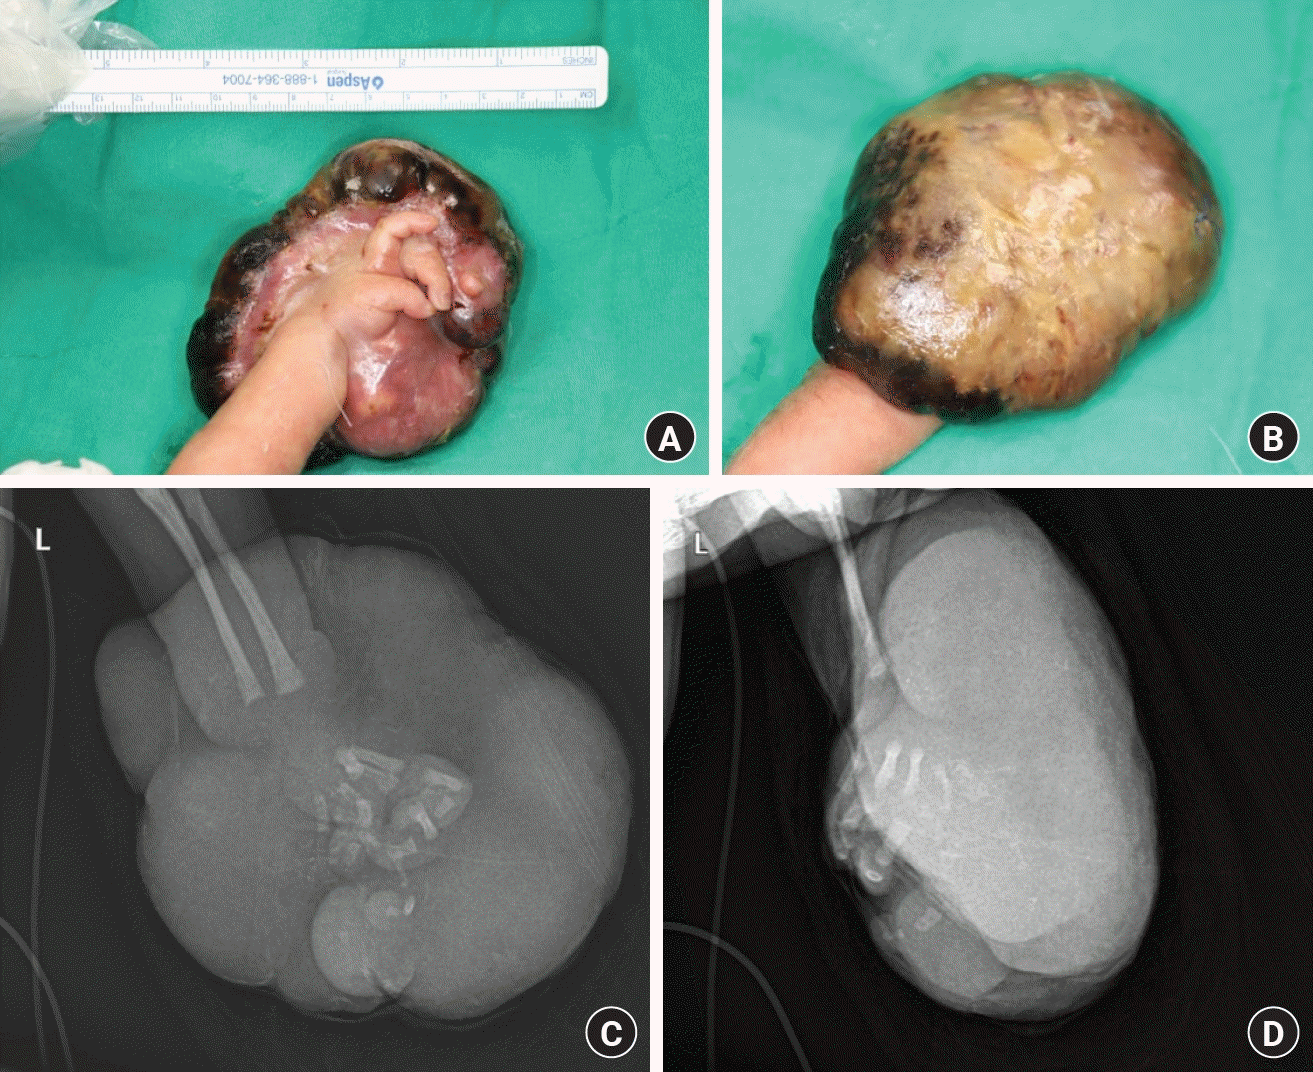

A male neonate, delivered by emergency C-section at 30 weeks and 4 days due to preterm labor with a birth weight of 2,228g, was referred to our institute at the age of 6 days for evaluation of a significant mass on the dorsum of his left hand (Fig. 1). Initial physical examination revealed an immature teratoma (10×12 cm) with signs of necrotic changes. Nodule-like masses were additionally observed on the right arm, both hips, and legs. Ultrasonographic examination revealed no pathological lymph nodes. Furthermore, the infant presented with hypocalcemia.

Upon collaborative deliberation, a surgical intervention was scheduled for the 8th day after birth. The surgical procedure, which lasted less than 30 minutes, was meticulously performed under general anesthesia without the use of a tourniquet, doppler, or microscope to minimize the anesthesia time. The tumor was excised, ensuring preservation of the hand’s dorsum, demarcating it from the presumed tumor boundary. The resection margin was determined based on the grossly visible tumor boundaries. The primary objective of the surgery was to reduce the massive tumor burden, with adjuvant chemotherapy (vincristine every week for 3 months) planned for any microscopic residual tumor. Frozen section pathology was not performed to minimize the anesthesia duration for the infant. The excised specimen weighed 160 g (Fig. 2).

Fig. 1.

Preoperative evaluation of the neonate’s lesion. (A, B) Gross photographs depicting the substantial mass on the dorsum of the left hand prior to surgical intervention. (C, D) X-ray images showing the internal structure and extent of the lesion on the affected arm, providing essential diagnostic information.